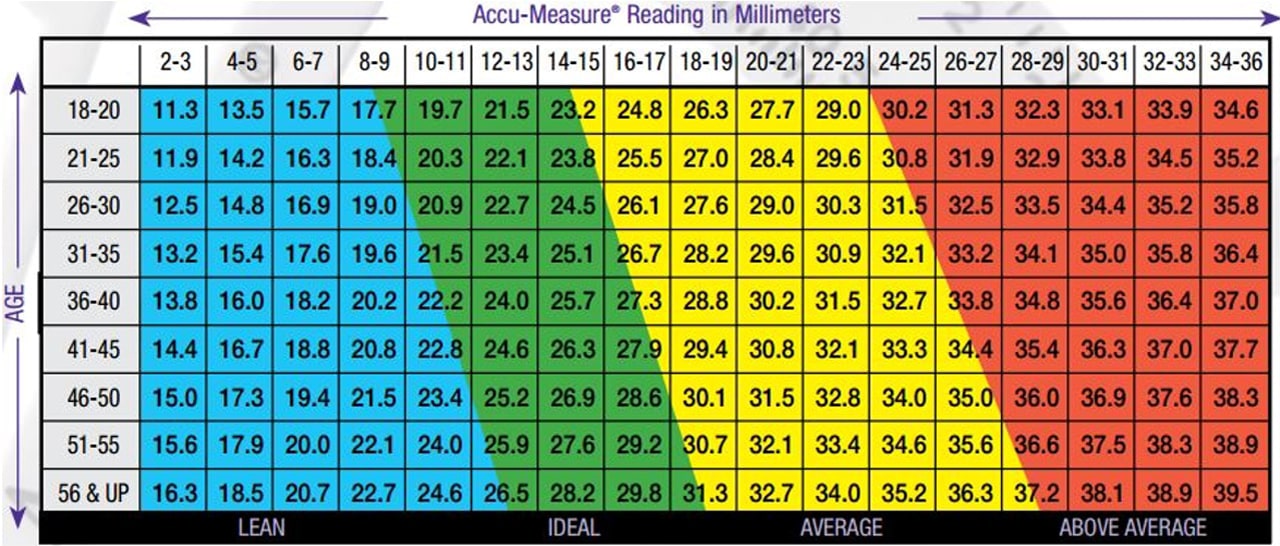

Hautfaltendicke (Calipometrie)

Bildquelle und weitere Infos zu dieser Methode finden sich hier:

Körperfettanteil berechnen: Wie viel Körperfett ist für Dich ideal? (marathonfitness.de)